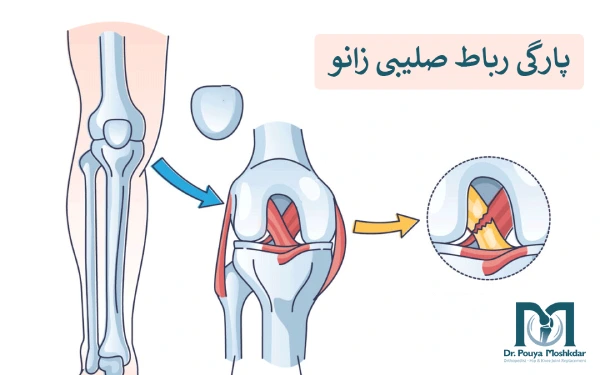

منظور از پارگی رباط صلیبی زانو چیست؟

پارگی رباط صلیبی زانو یکی از آسیبهای شایع مفصل زانو است که معمولاً در اثر پیچ خوردن ناگهانی یا ضربه شدید به زانو اتفاق میافتد.

رباطها ساختارهایی محکم و طنابمانند هستند که مفاصل بدن را در جای خود نگه میدارند و از حرکات غیرطبیعی جلوگیری میکنند. زانو به دلیل ساختار پیچیده و پویایش، توسط چهار رباط اصلی محافظت میشود که دو مورد از آنها یعنی رباط صلیبی قدامی و خلفی، به شکل ضربدری درون مفصل قرار دارند. نقش مهم این رباطها، کنترل حرکت ساق پا و تثبیت زانو در برابر حرکات ناگهانی یا شدید است. آسیب به این ناحیه میتواند موجب بیثباتی زانو و محدود شدن حرکت طبیعی آن شود.